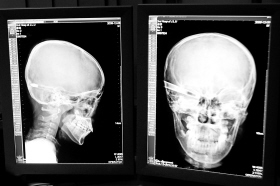

在接受x光檢查的小沖

“還是先做個(gè)X光透視,看一下箭桿到底有多深。”眼科醫(yī)生緊急趕到CT室查看,和放射科的幾位醫(yī)生共同研究后,決定先讓小沖做X光透視。

“如果再用點(diǎn)力,就從后腦穿出來了!”由于小沖無法移動(dòng),醫(yī)生拿來移動(dòng)插座,將透視的光板放在小沖的移動(dòng)病床上,透視后讓在場的醫(yī)生都吃了一驚:箭桿直接穿過了大腦和小腦,箭尖兒直抵后顱骨,足足有10余厘米。